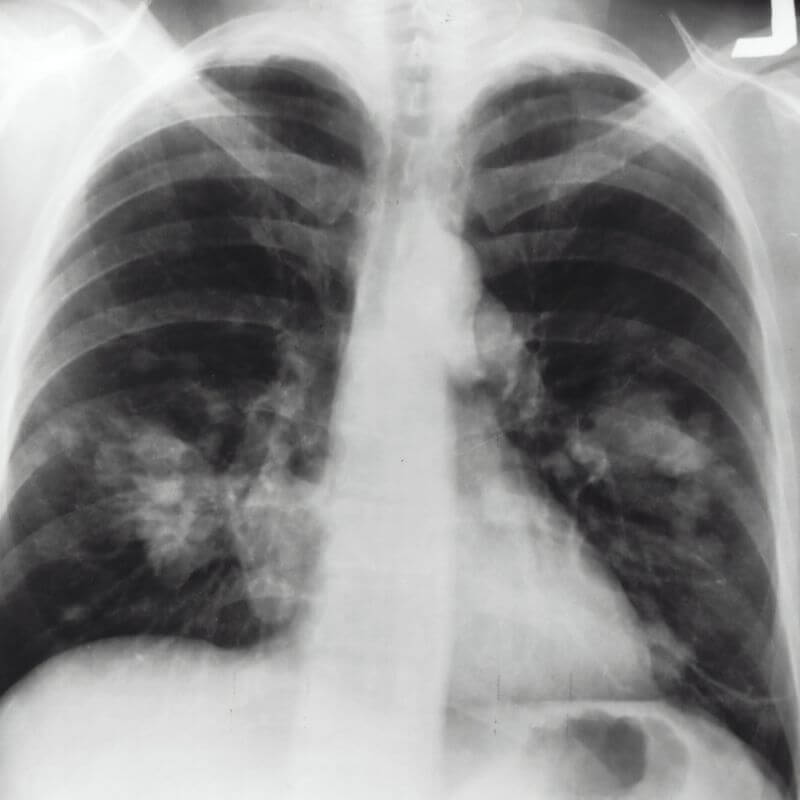

Los rayos X son un tipo de radiación electromagnética similar a la luz visible. Sin embargo, a diferencia de la luz, estos rayos tienen mayor